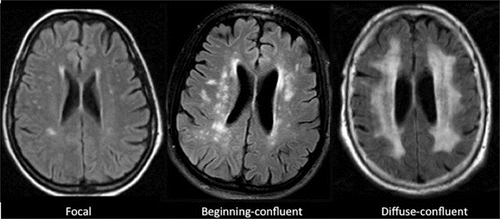

HBOT Treatment For White Matter Lesions

White matter disease is the wearing away of tissue in the largest and deepest part of your brain that has a number of causes, including aging. This tissue contains millions of nerve fibers, or axons that connect other parts of the brain and spinal cord and signal your nerves to talk to one another. A fatty material called myelin protects the fibers and gives white matter its colour. This type of brain tissue helps you think fast, walk straight, and keeps you from falling. When it becomes diseased, the myelin breaks down. The signals that help you do these things can’t get through. Your body stops working like it should, much like a kink in a garden hose makes the water that comes out go awry. White matter disease happens in older or elderly people. There are ways to prevent or even reverse this condition, but you need to start now.

There isn’t a specific treatment. The goal is to treat the cause of the damage and stop the disease from getting worse. Your doctor may prescribe medicines to lower your blood pressure or cholesterol There is evidence that White Matter Hyperintensities indicate Ischemia. Ischemia is the lack of blood flow to the small vessels in the brain. Ischemia can lead to poor oxygen supply and the death of tissue in the brain. Hyperbaric Oxygen Therapy is able to improve cognitive function of individuals with White Matter Hyperintensities by increasing the flow of oxygen to the brain and improving circulation.